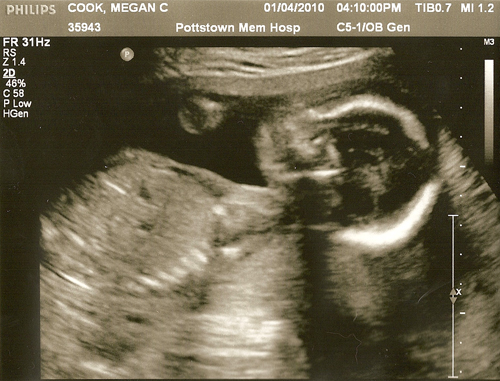

On January 4th, 2010 Megan and I visited the Pottstown Memorial Hospital for Lima’s second Ultrasound.

Honestly, it wasn’t as emotional for Megan and I ask Lima’s first Ultrasound – this was probably becauseĀ Megan couldn’t see the screen and I continued to ask why there were so many teeth. š Obviously baby’s don’t have teeth in the womb but I sware to you it looked like a xray ((yes, I know we were at an Ultrasound – trying to make a point here)) of someone’s upper and lower teeth.Ā Sometimes with a third row in the middle.Ā I believe this was probably the spine andĀ a weird Ultrasound reflection issue that has some technical name attached to it.

Anyway, here are pictures!